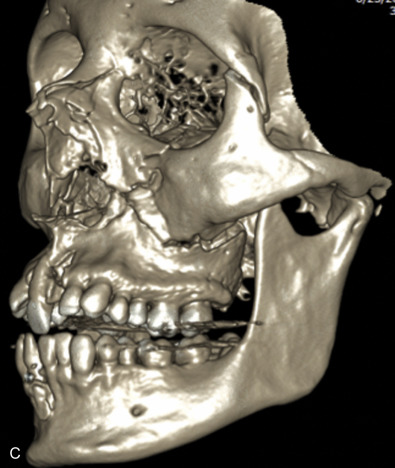

The gold standard for radiographic evaluation is thin-slice helical computed tomography (CT). Midface fractures are confirmed by axial, coronal, and sagittal views. The degree of comminution, bone loss, and detailed images of the fracture patterns can be assessed and juxtaposed to surrounding soft tissue structures. 3D reconstruction, when utilized, can aid in visualizing the complex 3D anatomical orientation of fracture fragments that occur in Le Fort injuries and facilitate reconstructive planning.

Le Fort III fractures generally consist of a combination of fractures that involve the palatine bones, the maxilla, the pterygoid plates, the nasal bones, lacrimal bone, and zygomas; they essentially separate the face along the base of the skull. The fracture pattern extends through the nasofrontal suture along the medial wall of the orbit, through the inferior orbital fissure and the lateral orbital wall to the zygomaticofrontal suture. In addition, the zygomaticotemporal suture is separated. The fracture extends across the sphenoid bone resulting in dysjunction at the pterygoid plates ( Figs. 1.13.16 and 1.13.17 ). The septum is separated from the cribriform plate of the ethmoid. Pure Le Fort III fractures are rare, and in actuality, most are ZMC fractures in conjunction with Le Fort I and II fractures lending the appearance of a comminuted “Le Fort III.” The force is delivered from the orbital level, resulting in craniofacial dysjunction. The fracture is generally more comminuted and more extensive on the side of force application.